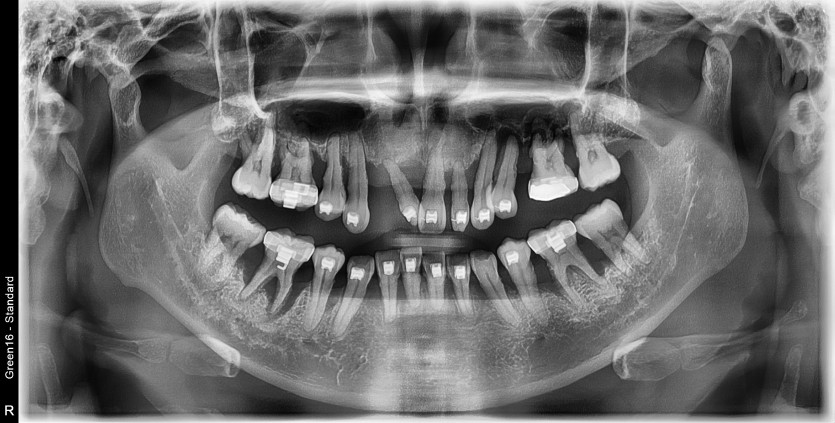

전체 임플란트 증례입니다.

18개의 임플란트로 완성하였습니다.